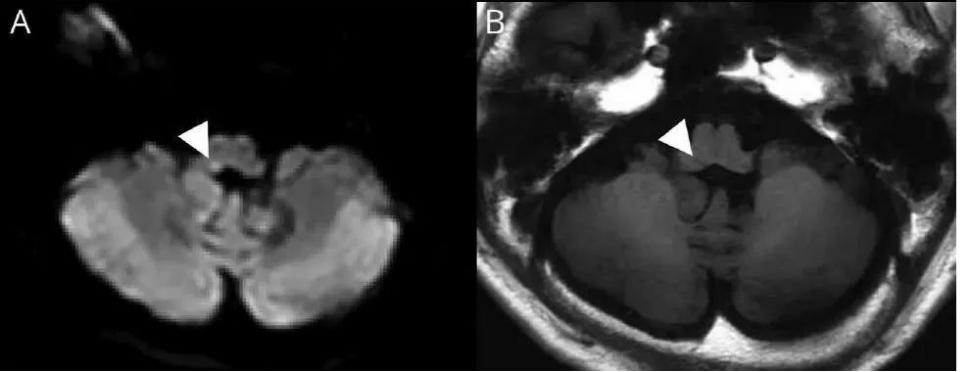

病例:76岁,男性。因呃逆4 d就诊。否认头晕,感觉异常或无力。MRI显示右侧延髓背外侧疑核和迷走神经核区急性梗死:

图3 以呃逆为主要症状的脑梗死患者颅内病变情况A. DWI;B. T1;C. T2;D. FLAIR